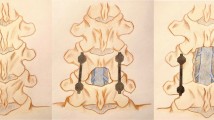

The anteroposterior vertebral slip and intervertebral disc angle were measured on lateral radiographs of the L3–4 and L4–5 taken in the neutral, flexion, and extension positions. To minimise the errors due to different magnifications, the vertebral slip was expressed as a percentage of the caudal vertebral body width (% slip). The ranges of motion (ROM) of the L3–4 and L4–5 segments were defined as the sum of the intervertebral disc angles in the flexion/extension view (Fig. 1). Pseudarthrosis was present if there was no continuity in the PLF fusion mass between the cephalad and caudad transverse processes, no continuity between graft bone and vertebra in PLIF fusion, or if lateral flexion–extension radiographs demonstrated >2° of angular motion or >2 mm of sagittal motion at L4–5 [11].

Plain radiography measurement. a Anterior slip in the flexion position, b posterior slip in the extension position, c vertebral body width. The total percent slip is (a + b)/c × 100. α Intervertebral disc angle in flexion position, β intervertebral disc angle in the extension position. The range of motion is α + β in degrees